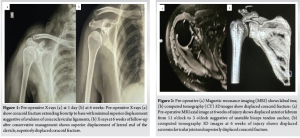

A 48-year-old female presented to the emergency room with a complaint of a fall from a height. Following the incident, the patient experienced retrograde amnesia and substantial pain in her right shoulder and hand while moving. Upon arrival, she was hemodynamically stable but was in significant discomfort. She was initially diagnosed with a right coracoid fracture and had a history of rheumatoid arthritis, for which she was receiving long-term treatment with hydroxychloroquine. During the initial evaluation, she had tenderness around the coracoid process of the right shoulder with severe painful restriction of shoulder movements. She also had symptoms and signs suggestive of a concussion injury to the brain. She had normal systemic examinations. Radiological investigations included a magnetic resonance imaging (MRI) of the cervical spine, revealing straightening due to paraspinal muscle spasm and mild posterior bulging of the C3-C6 discs without significant foraminal compromise. A computed tomography (CT) scan of the brain ruled out acute intracranial pathology. A CT scan of the thorax identified a displaced coracoid process fracture, and a right shoulder CT confirmed a double fracture of the coracoid process. However, the associated ACJ dislocation was left undiagnosed in the initial evaluation. The patient was managed conservatively with standard analgesia and a shoulder immobilizer. Despite adherence to conservative treatment, persistent pain and functional limitations were noted in subsequent follow-ups. A 6-week follow-up X-ray revealed non-union of the coracoid fracture along with ACJ dislocation, which had been previously undiagnosed. Further evaluations showed significant shoulder instability, persistent pain, and muscle wasting, with restricted movements in forward flexion, abduction, and external rotation.(Fig. 1 ). An MRI of the right shoulder later confirmed an anteroinferior labral tear, a small Hill-Sachs lesion, and ACJ dislocation. A fresh CT scan showed a double fracture of the coracoid extending to the base with superior displacement of the ACJ. Multiple ipsilateral rib fractures were also identified. Given the failed conservative management, a multidisciplinary team recommended surgical intervention.(Fig. 2 )